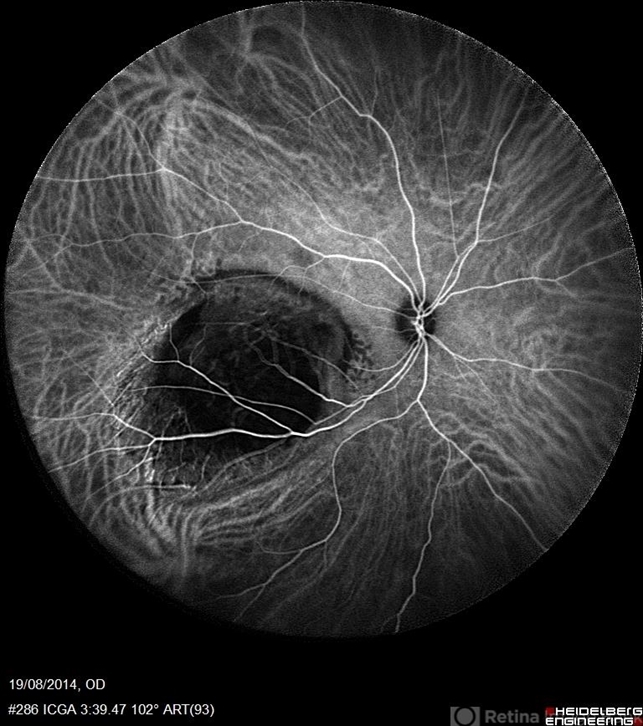

- indocyanine green (ICG) angiography, ultra-wide field imaging, choroidal tumor

- Avris Romario Diparaja Siahaan, Klinik Mata Nusantara

Scanning laser ophthalmoscope

Heidelberg Spectralis - Description

- An ICG Angiography photography of a 27-year-old woman with a choroidal tumor in her right eye.